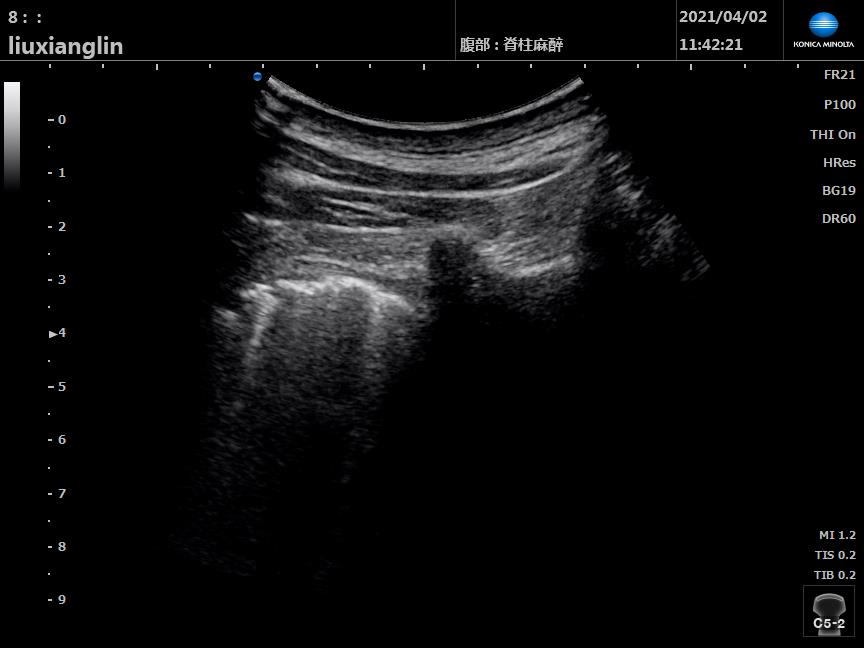

▲超声实时监测 灌洗侧肺超声声像可见“肺间质综合征→肺水肿→肺实变”